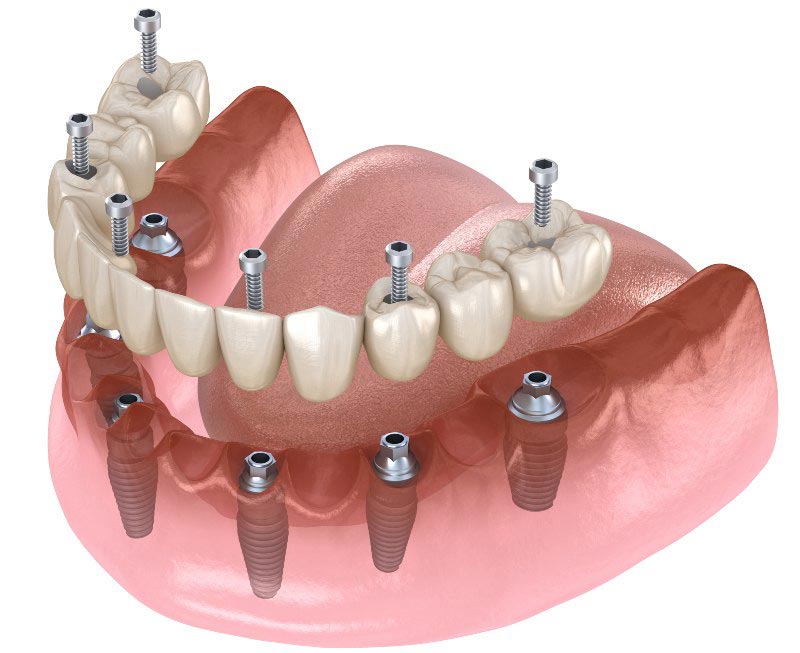

هزینه ی پروتز دندان به عواملی مانند وضعیت دهان و دندان بیمار، نوع پروتز دندان، جنس مواد به کار رفته برای ساخت پروتز، هزینه مرکز دندانپزشکی و تخصص دندانپزشک بستگی دارد. پروتز دندان ناکامل یا پارشیل برای افرادی مناسب است که تنها تعدادی از دندانهایشان را از دست داده اند. اما پروتز کامل برای افرادی مناسب می باشد که دندان های خود را به صورت کامل از دست داده اند. انواع پروتز ثابت شامل روکش دندان، بریج دندان، پروتز ثابت بر پایه ایمپلنت می باشد. گاهی اوقات امکان استفاده از پروتز ثابت وجود ندارد. در این مواقع، دندانپزشک استفاده از پروتزهای متحرک را پیشنهاد می کند. پروتز متحرک را می توانید هر موقع خواستید داخل دهان بگذارید و بردارید. بنابراین، پروتز متحرک می تواند برای عده ای از افراد بهتر از پروتز ثابت باشد.